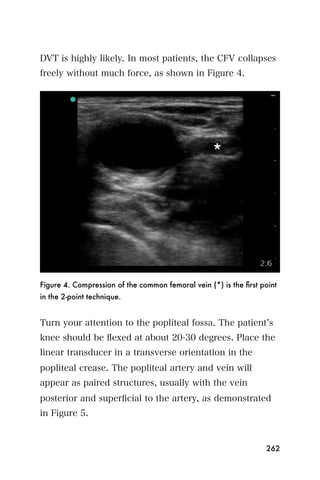

5. Fox H. The development and structure of the placenta. In: Fox

H, ed. Pathology of the placenta. 2nd ed. London, England: WB

Saunders, 1997: 1-41.

6. Hadlock FP. Sonographic estimation of fetal age and weight.